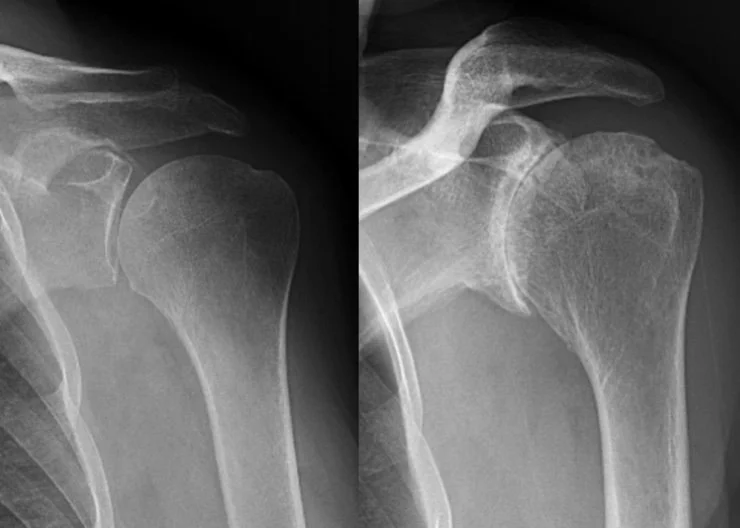

Arthritis (osteoarthritis) of a joint is a condition where the cartilage in the joint is damaged. In the beginning, there may be only slight cartilage loss but as the condition progresses, all the cartilage in a joint can be lost leading to a "bone on bone" situation. To understand arthritis, we need to know the characteristics of cartilage.

A thorough visit with a physician and basic x-rays can usually make the diagnosis clear. In the early stages of the condition, cartilage damage may only be seen on MRI (so called chondromalacia). It is important to evaluate for other causes of joint pain that can mimic osteoarthritis (i.e. gout, infection, meniscus tear, ligament tear).